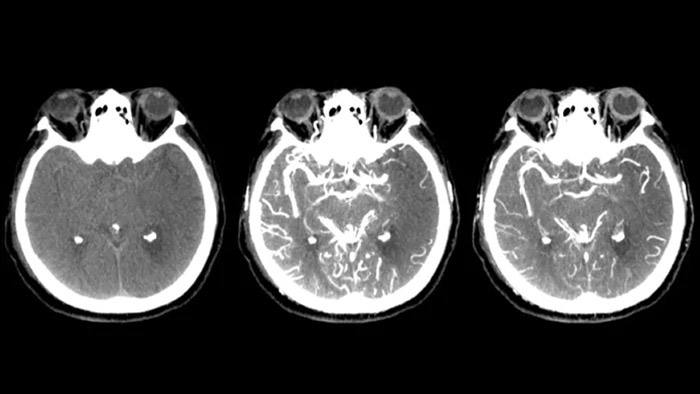

SmartCT Soft Tissue выполняет КТ-подобную визуализацию мягких тканей и дополняет диагностику инсульта тремя способами. Технология бесконтрастного сканирования помогает выявить ишемические изменения на ранних стадиях. Сканирование ранней фазы помогает определить проксимальную окклюзию. Сканирование поздней фазы с усилением контраста направлено на обнаружение коллатералей.

SmartCT Vaso позволяет проводить визуализацию за пределами тромба с помощью перипроцедурного создания изображений дистальных сосудов при ишемическом инсульте. SmartCT Vaso — это метод сбора данных, основанный на получении КТ-изображений с помощью конического пучка и внутриартериальной инъекции контраста. Технология позволяет проводить визуализацию за пределами тромба с помощью перипроцедурного создания изображений дистальных сосудов при ишемическом инсульте. При ретроградном наполнении становится видна структура сосудов до и после тромба. 3D-схема сосудов SmartCT Vaso может использоваться при визуализации устройств для извлечения тромба.

Технология Dual View для одновременного просмотра ранней и поздней фаз КТ-подобной визуализации способствует определению ишемической полутени и обеспечивает визуализацию наполнения коллатералей.